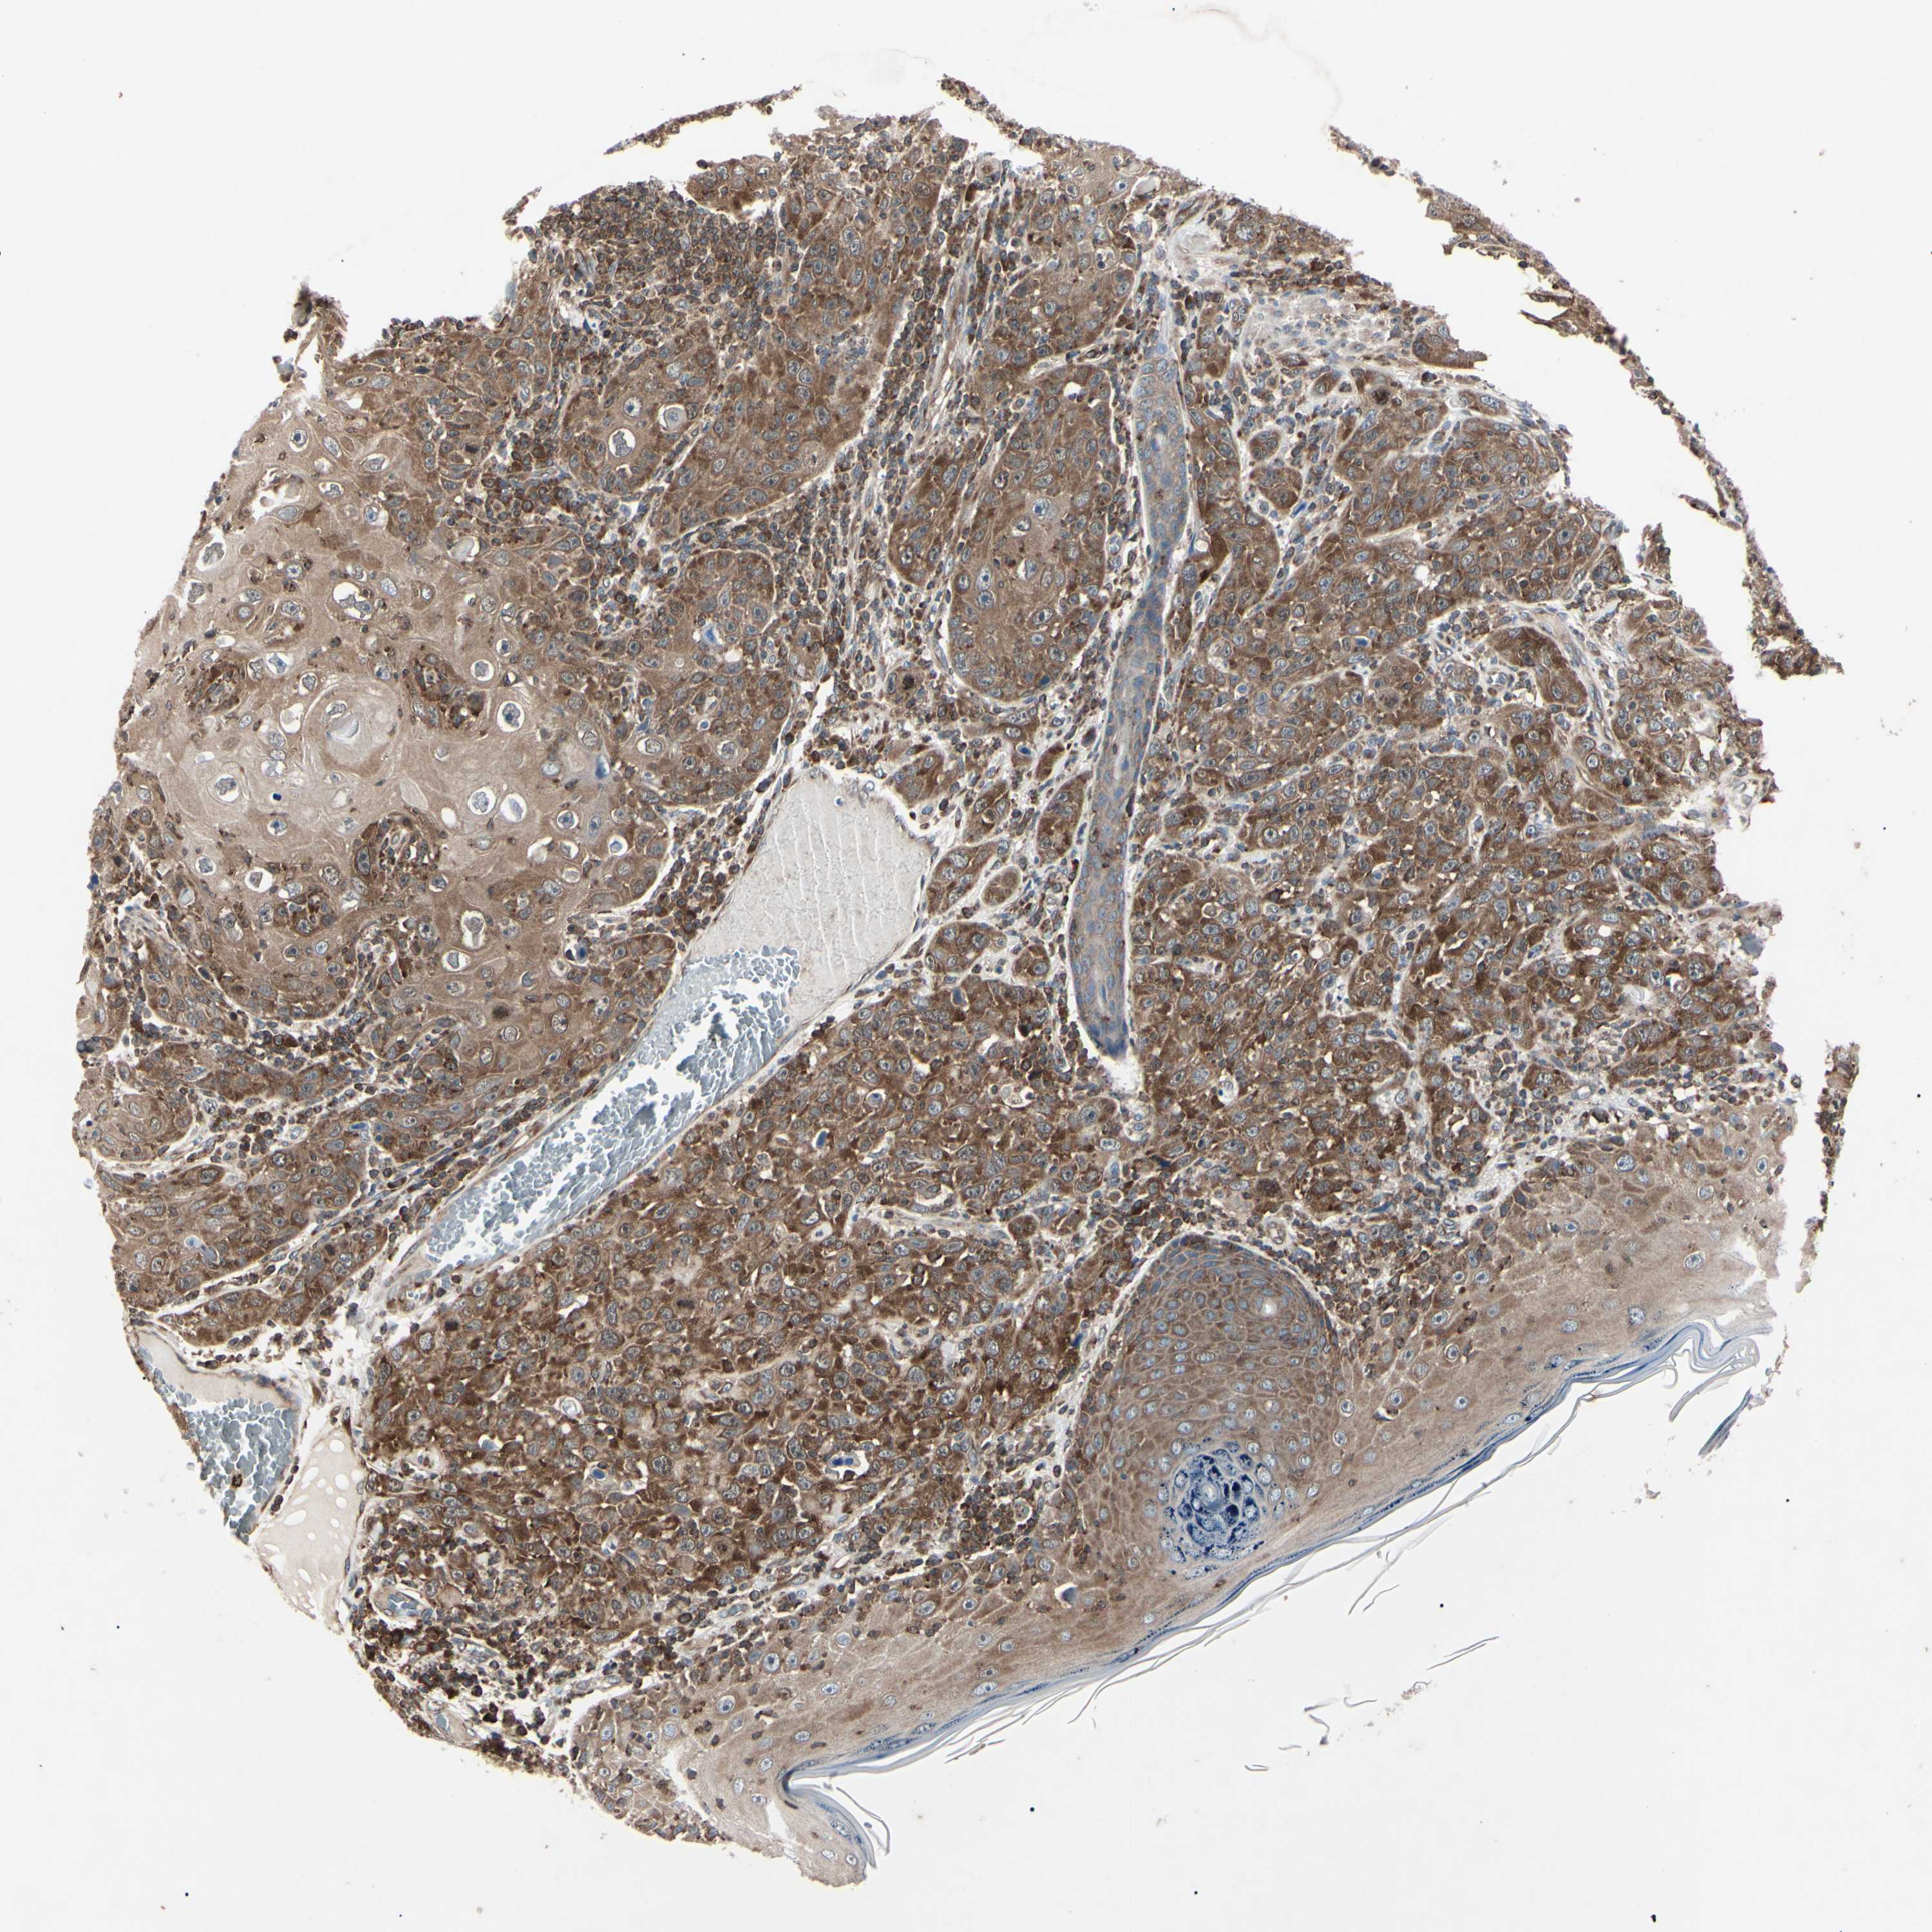

Basal cell and squamous cell cancer

SKIN CANCER - Protein expressioni

A mouse-over function shows sample information and annotation data. Click on an image to view it in a full screen mode. Samples can be filtered based on level of antibody staining by selecting one or several of the following categories: high, medium, low and not detected. The assay and annotation is described here.

Antibody stainingi

Antibody staining in the annotated cell types in the current human tissue is reported as not detected, low, medium, or high, based on conventional immunohistochemistry profiling in selected tissues. This score is based on the combination of the staining intensity and fraction of stained cells.

Each image is clickable and will lead to virtual microscopy that enables deeper exploration of all samples and also displays staining intensity scores, fraction scores and subcellular localization as well as patient and tissue information for each sample.

Antibody HPA003600

Staining

High

Intensity

Quantity

Location

Squamous cell carcinoma, NOS